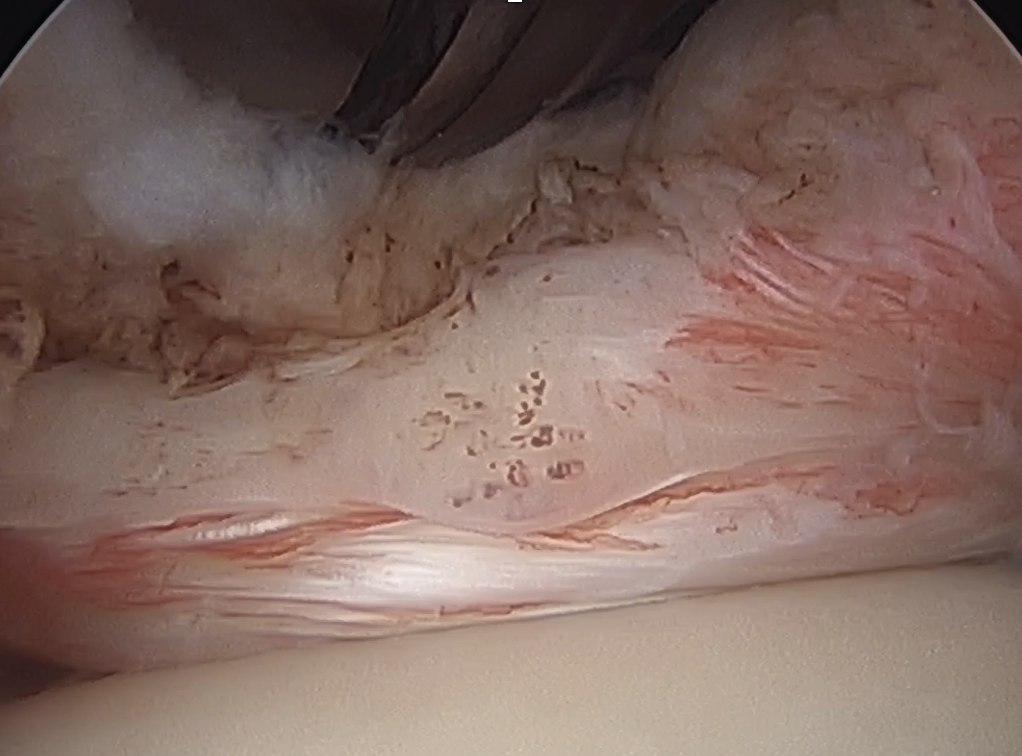

Arthroscopy

Hidden lesion

- assess subscapularis insertion thoroughly

- beware medial subluxation of the biceps

Medially dislocated biceps tendon with upper border subscapularis tear

Full thickness tear of subscapularis off insertion revealed with grasper